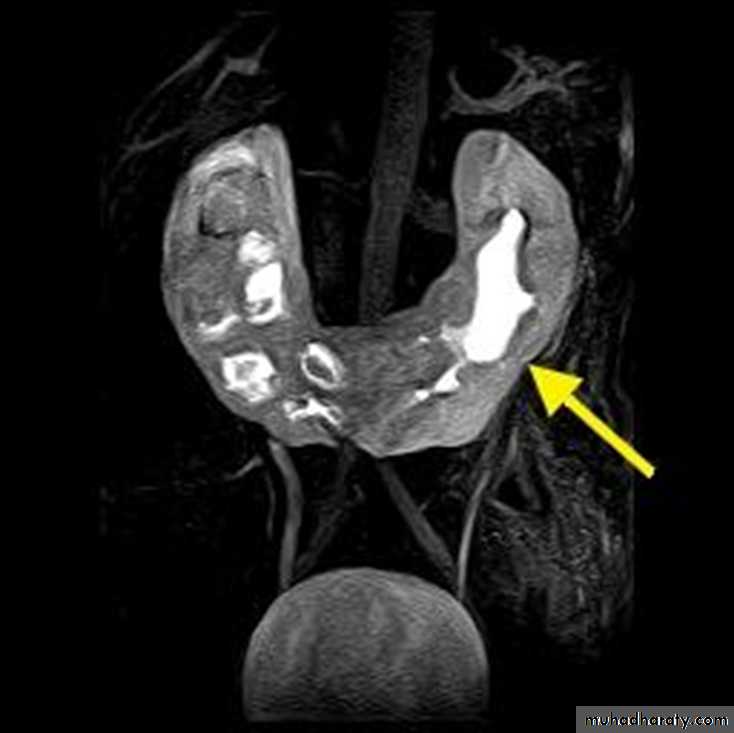

Horseshow kidney

Horseshoe Kidney

Horseshoe kidney occurs in 1 of 400 of the population.It is found more commonly in males.

In 95% of cases, the kidneys join at the lower pole, rarely isthmus connects at upper poles.

Generally, the isthmus is bulky and consists of parenchymatous tissue with its own blood supply . Occasionally it is composed of fibrous tissue.

Migration is usually incomplete, with the kidneys lying lower in the abdomen than normal. It is presumed that the inferior mesenteric artery prevents full ascent by obstructing the movement of the isthmus